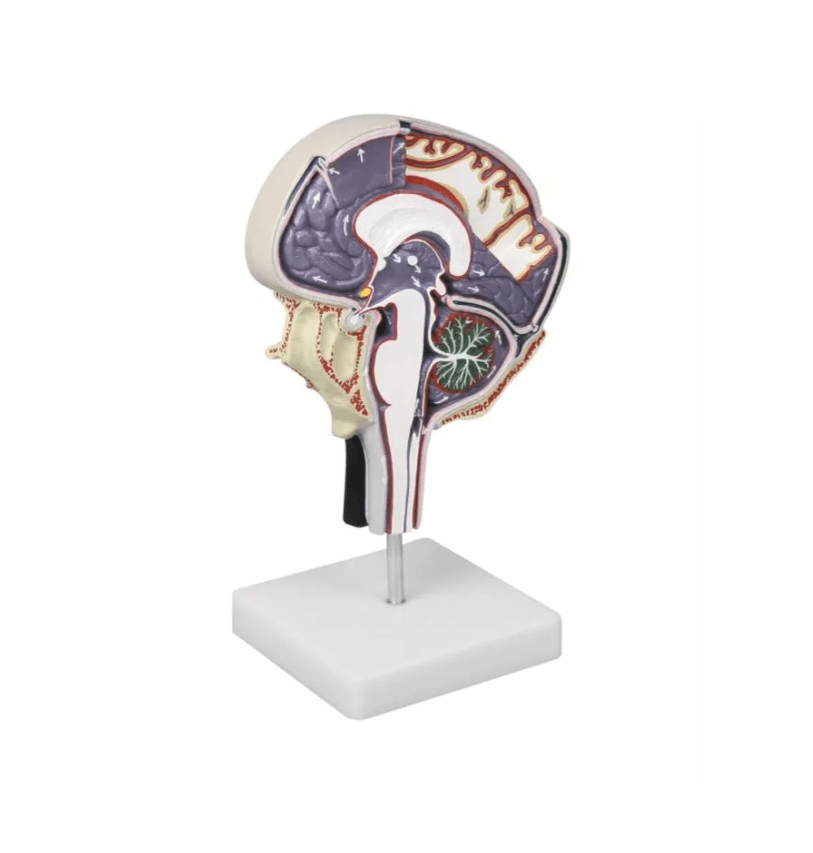

Erler-Zimmer

Hirnflüssigkeitskreislauf

Artikelnummer: SKU: EZC76

PZN: PZN:

Packaging unit: VE:

Auf Lager: In 1–3 Werktagen geliefert

★★★★★ 0 Bewertungen615,00 €615,00 €615,00 € -